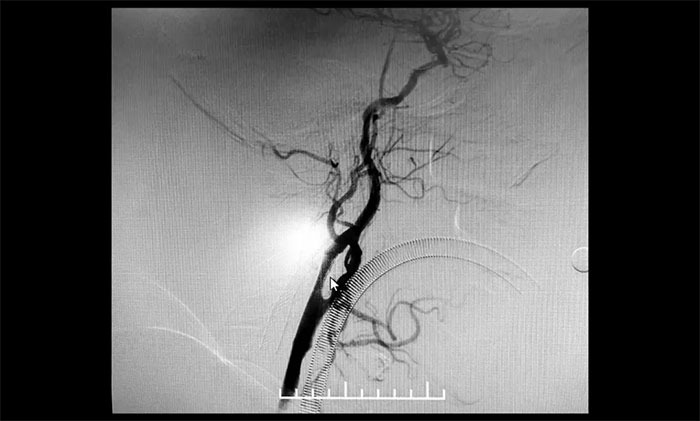

术后康复观察一月余,于耀宇主任团队再次为曹老伯行右侧颈动脉支架置入及左侧椎动脉支架置入手术。术中造影显示,右侧颈内动脉起始段重度狭窄,狭窄长度8mm左右。左侧椎动脉 V4 段重度狭窄,长度6mm左右。运用娴熟扎实的技术,在充分做好脑保护的前提下经过多次球囊扩张后,顺利释放支架于狭窄处。造影提示支架打开良好,血管狭窄基本恢复正常,支架贴壁佳,支架内血流通畅,远端血流良好。

▲ 术后,右侧颈内动脉及左侧椎动脉狭窄明显改善